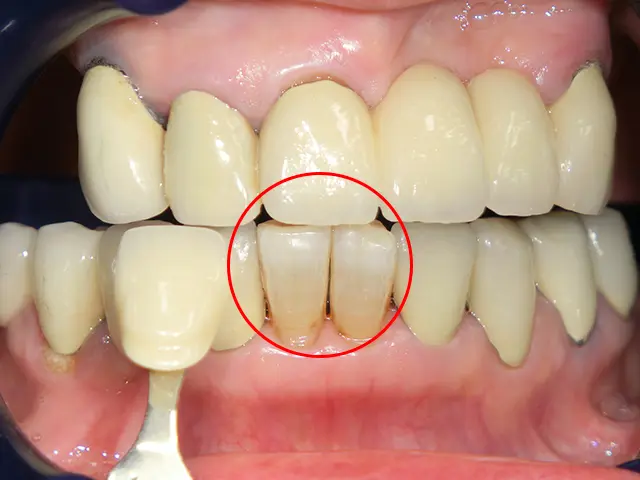

歯肉退縮、根露出の著しい場合はホワイトニングを行うことができません。患部にしみたり、痛みが出る可能性が高くなります。

症例 3

初診時

治療後

| 年齢 | 30代男性 |

|---|---|

| 主訴 | 歯の黄ばみを改善したい |

| 治療内容 | オフィスホワイトニング |

| 施術時間 | 1回(2時間程度)、施術前のクリーニング含む |

| 費用 | 24,300円 |

| 考えられるリスク | 施術直後に一過性の知覚過敏を生じることがある。 |